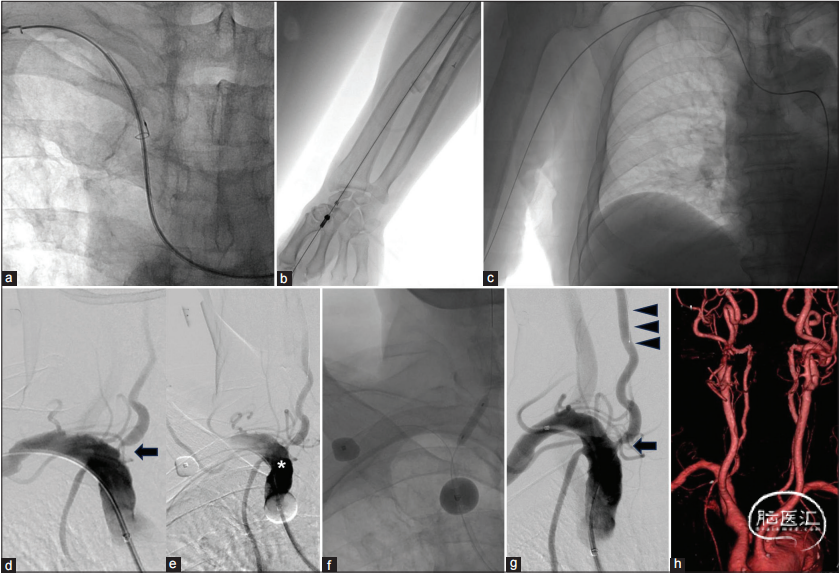

为预防A-to-A栓塞的复发,使用双抗血小板治疗(DAPT),并于发病后20天选择性地进行了VAOS的PTA。术者使用Mo.MA™ Ultra血流反向脑保护装置。术前CTA显示主动脉弓III型和右侧头臂动脉(BRCA)明显扭曲,术者采用了牵引技术(2a-c):

首先,穿刺左侧股动脉,放置了一个9Fr导管(Terumo,东京,日本),使用4Fr SIM2 120cm(Medikit,东京,日本)/导丝surf 0.035 180cm(Piolax,神奈川,日本),选择右BRCA。

然后,穿刺右桡动脉(RA),放置了一个5Fr导管(Terumo,东京,日本)。使用右RA路径,使用Amplatz Goose Neck™ Microsnare(Medtronic,都柏林,爱尔兰)在右肱动脉放置了一个SIM 2(图2.a)。

为了创建Mo.MA™ Ultra的牵引路径,术者通过SIM 2和右RA的5Fr导管使用Amplatz Goose Neck™ Microsnare放置了Radifocus®硬导丝0.035 300cm(Terumo,东京,日本)(图2.b和c)。穿刺右侧股动脉,放置一个用于血流反向的4Fr导管,并通过该路径将Mo.MA™ Ultra放置到右BRCA。

在使用Mo.MA™ Ultra过程中,使用肝素维持激活凝血时间在250秒以上,确认Mo.MA™ Ultra的位置和血流反向保护作用(图2.d和e)。使用SL-10 150cm(Stryker,密歇根州,美国)/CHIKAI 0.014 200cm(Asahi intecc,爱知,日本)跨越病变,并将CHIKAI放置到右VA的V2−V3部分。术者连接CHIKAI延伸到CHIKAI,放置了Gateway 3.5×15mm,并进行了PTA(10atm,标称压力6atm,30s)(图2.f)。在PTA后,右BRCA造影显示VAOS和VA血流有所改善(图2.g)。BRCA造影后15分钟确定了VAOS和VA血流有所改善。在随访磁共振成像中未检测到与治疗相关的梗死,右VAOS血流改善得以保持(图2.h)。患者在发病后42天出院,并在PTA后28天转至康复医院。

图2.(a-c)使用Radifocus®硬导丝,通过Amplatz Goose Neck™ Microsnare制作牵引路径以放置Mo.MA™ Ultra。在数字减影血管造影中,(d)可见VAOS(箭头),并被认为是A-to-A栓塞的原因。在血流反向保护下,对比剂(星号)通过右VA向血流反向汇集(e)。(f和g)进行经皮腔内血管成形术,以改善VAOS(g,箭头)和右VA的血流(g,箭头)。(h)通过随访计算机断层血管造影确认右VA中VAOS通畅。